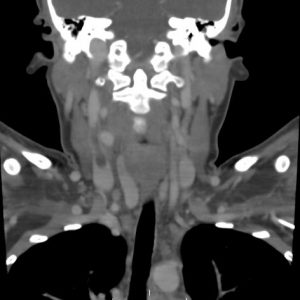

A deep vein thrombosis that is isolated to the calf veins is considered to be different than a deep vein thrombosis that is located in the popliteal vein or more proximal at the level of the thigh or pelvis. Calf vein thrombi are often referred to as “distal DVT” as to differ them from proximal…